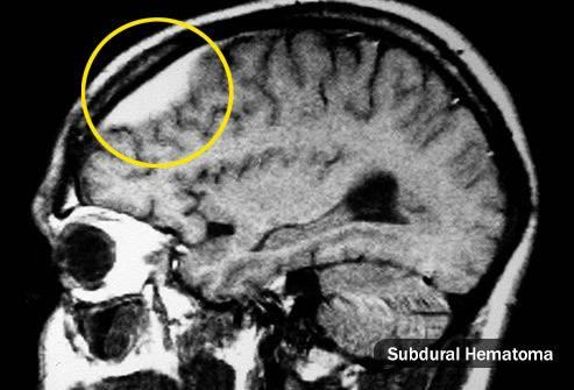

يسبب صداع التوتر الشعور بألم خفيف وضيق أو ضغط حول الجبهة أو مؤخرة الرأس والرقبة وقد يصفه بعض المرضى بالمشبك الذي يضغط على الجمجمة وهو أكثر أنواع الصداع شيوعا بين البالغين. Headache كما أن الأشخاص المصابون بالصداع غالب ا ما يجدون صعوبة في النوم ومن الملاحظ أن النوم المتقط ع لعدة ليال قد يجعل الناس أكثر عرضة. فلدى نحو 70 من الذين يعانون من الصداع النصفي قريب من الدرجة الأولى يعاني منه كما أن أقارب من الدرجة الأولى للشخص الذي يعاني من الصداع النصفي أكثر. ماذا تعرف عن صداع.